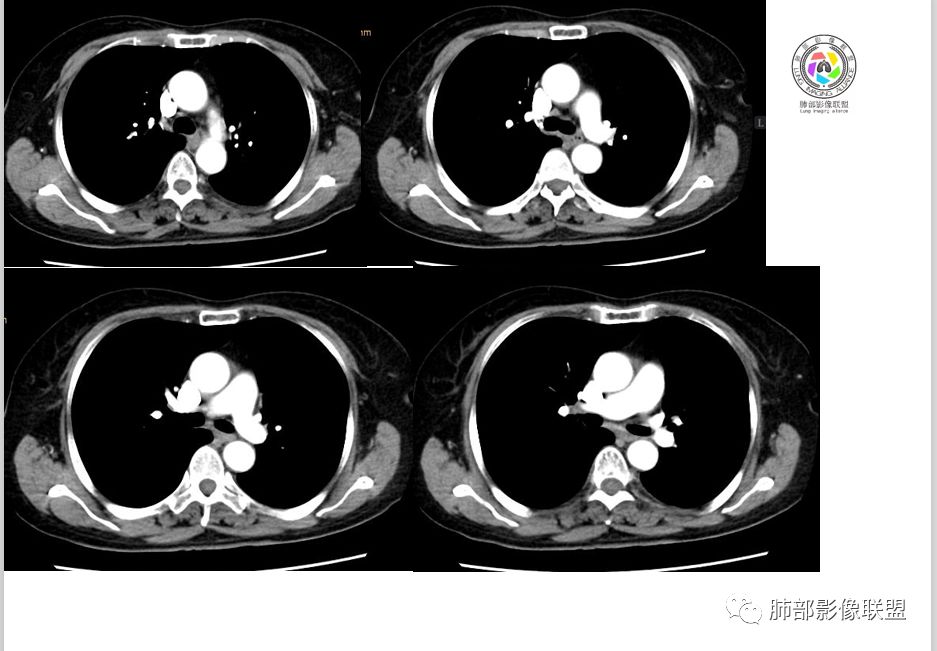

Coke with ice:PSP?M-Imaging :良性,PSPShelia:左肺下叶肿块,边缘光整,有血管贴边征,支气管受压推移,延迟强化,考虑PSP?鉴别类癌。不除外恶性

左手:老年女性,无特殊症状,左下肺类圆形结节,边缘清晰,增强见血管贴边,明显强化,无深分叶,无钙化,考虑pspForever:晨读病例病变与血管关系密切 确实psp首先考虑,类癌,腺癌,纤维瘤不能除外没意见:PSP,类癌待排徐超:psp

支气管无关,圆形,光滑,贴别血管稍粗,磨玻璃晕(出血),强化中度,支气管旁疑推挤非阻塞……良性

小木:考虑psp妞妞:支持PSP德芙~云味:考虑psp红日东升:支持PSP崔刚:强化具体CT值忘了标注,轻度强化

目前大家意见一致一米阳光:左肺下叶类圆形病灶,边缘清晰,密度均匀,无分叶毛刺等恶性征像,增强,病变明显强化,血管贴边支持PSP,鉴别类癌,后者弱强化,貌似有分叶南边:

崔刚:当时写报告看好像是支气管确实没堵,受压的改变。

横断位应该显示了这个支气管,当时记得特意考下来图了

M-Imaging :周围有黑边,错构呢?南边:如果明确没堵塞就好办这个最主要的就是这个支气管是否堵塞没堵塞,支持PSP杨泽锋:如果是气管腔内起源的那就要考虑类癌M-Imaging :不见明显冰山征,没有钙化南边:心里不是很踏实,就是没看到支气管全景Forever:强化如果不高 我还是考虑小细胞肺癌或者腺癌

崔刚:有个层面支气管在病灶周边Yiren  Sishui(厶水伊人):其实就是PSP与类癌的鉴别M-Imaging :Forever:如果分不清结构关系了 这个时候强化还是有很大参考价值M-Imaging :周围有黑边崔刚:没有钙化和脂肪,张老师是不是考虑错构瘤?徐超:黑边是想说错构瘤M-Imaging :是啊滴水海:psp也可Forever:不像 觉得ct值有点高。一般错构瘤ct值低于20,没有钙化

滴水海:有黑晕更支持pspM-Imaging :黑边代表局限肺气肿错构瘤,应该和血管没有关系,这例血管贴近毛勤香:考虑PSP或错构瘤,类癌代排南边:我的判断原则:支气管无关——良性、间叶来源良性,强化明显——PSP,尤为明显——糖瘤,不明显——错构瘤

wonderful:纵膈有吗徐超:隆突下没有肿大淋巴结。思路没问题,主要还是支气管的关系。还有CT值,有测量值最好。强化不同疾病范围不同,虽然有叠加Coke with ice:这个病灶好像有浅分叶,是否有鉴别意义呢南边:可能绕过去了。浅分叶没什么价值,深分叶有Forever:动脉期强化不太均匀 而且ct值不高我觉得有提示意义

M-Imaging :PSP强化应该达到一百多吧

1.肺内如此大小的周边较光滑的孤立结节影或块影,密度较均匀的,一般会想到硬化性肺细胞瘤、错构瘤、小细胞癌、大细胞癌、类癌,以及单发转移灶等。

2.边缘光整,坏死不明显,未显示阻塞性炎症或不张,女性患者,肺鳞癌不支持。

3.缺乏典型深分叶及毛刺,强化不显著,似乎也缺乏肺腺癌的影像学特点。

4.未见脂质密度及钙化,强化程度等均不支持错构瘤。

5.同样病灶轻到中度强化也不支持类癌及大多数的硬化性肺细胞瘤(血管瘤样区为主)。

后者不能排除,毕竟不是所有的硬化性肺细胞瘤强化都那么显著。

6.转移瘤缺乏相关临床支持。

7.病灶的形态及强化程度都不能排除小细胞癌及大细胞癌,纵隔尤其是隆凸下未见增大淋巴结似乎不符合小细胞癌等的生物学行为。